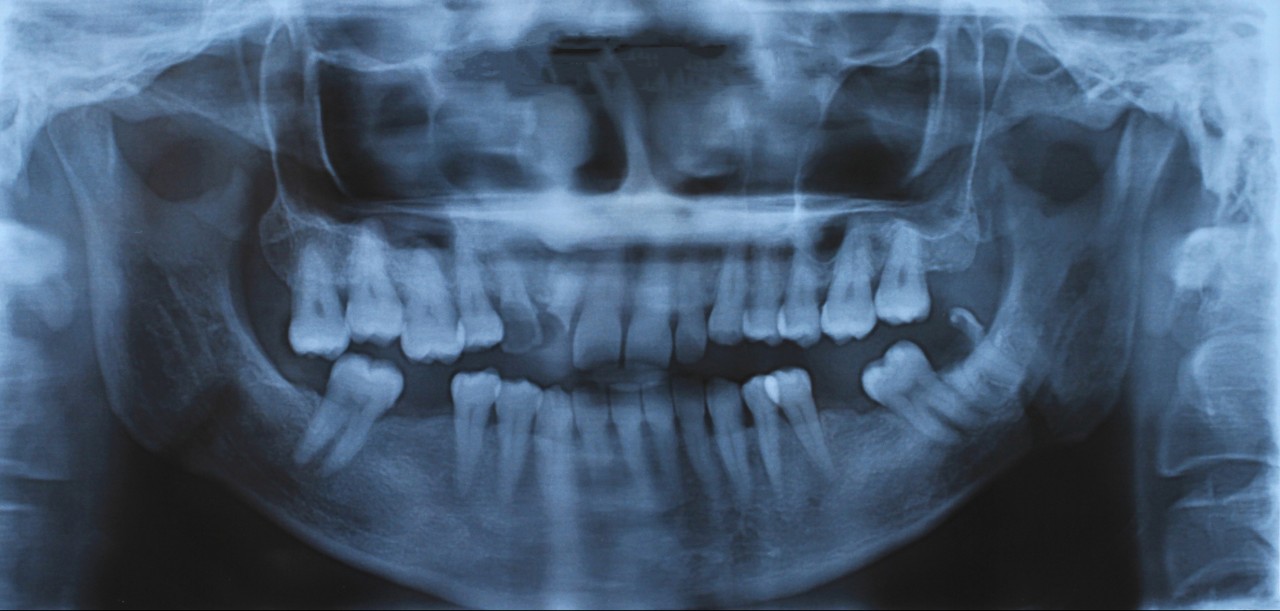

Other comparison procedures fared less well. For example, despite formal qualifications in dentistry and forensic experience, forensic dentists can’t reliably link a bite mark on human skin with specific teeth. Indeed, they can’t even determine whether marks on skin are bite marks.

Matching a set of teeth to bite marks isn’t as straightforward as movies would have you believe. Shutterstock